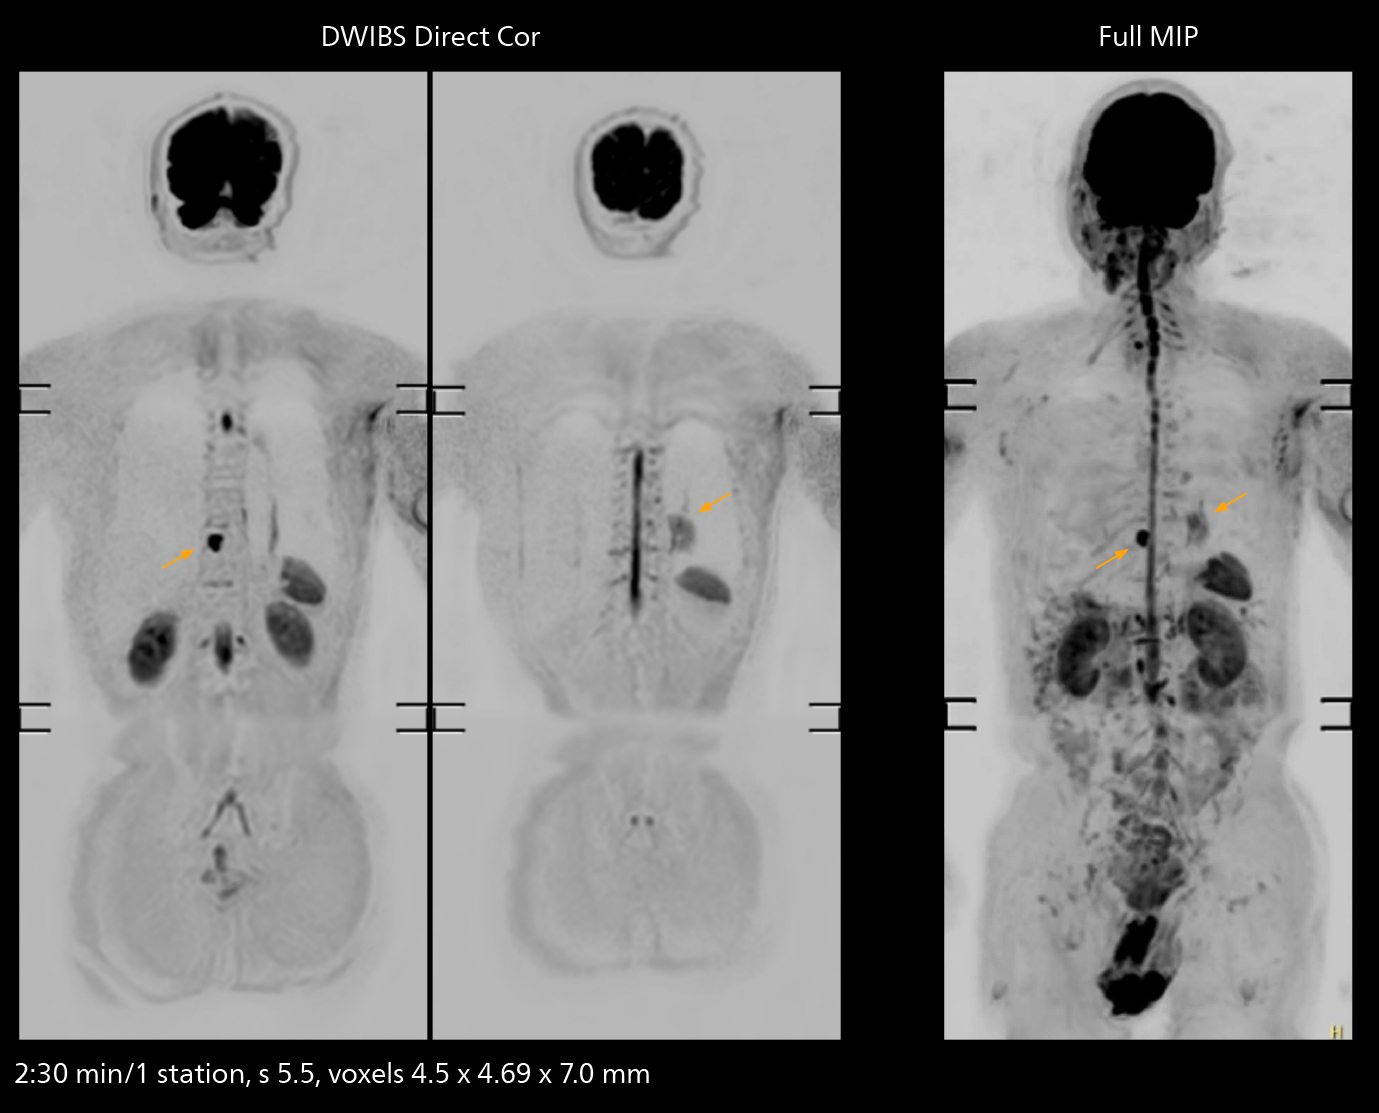

The value of the Elition X gradients is also evident in DWIBS studies. “The fact that we can consistently obtain distortion‐free DWIBS while reducing imaging time at three coronal stations is excellent,” Dr. Makuuchi says. “In these patients, it’s also important that the application of Compressed SENSE to T2‐weighted, STIR and mDIXON sequences has no impact on the examination time of whole‐body imaging. As a result of the increased speed and higher image quality we realize, DWIBS studies have now become routine examinations.”

Fast whole body DWIBS examination

With SmartPath to Elition X the team can obtain excellent quality DWIBS imaging and reduce imaging time. Other sequences also fit in the examination slot. This case shows left paravertebral neurogenic tumor and Th10 vertebral hemangiomas.